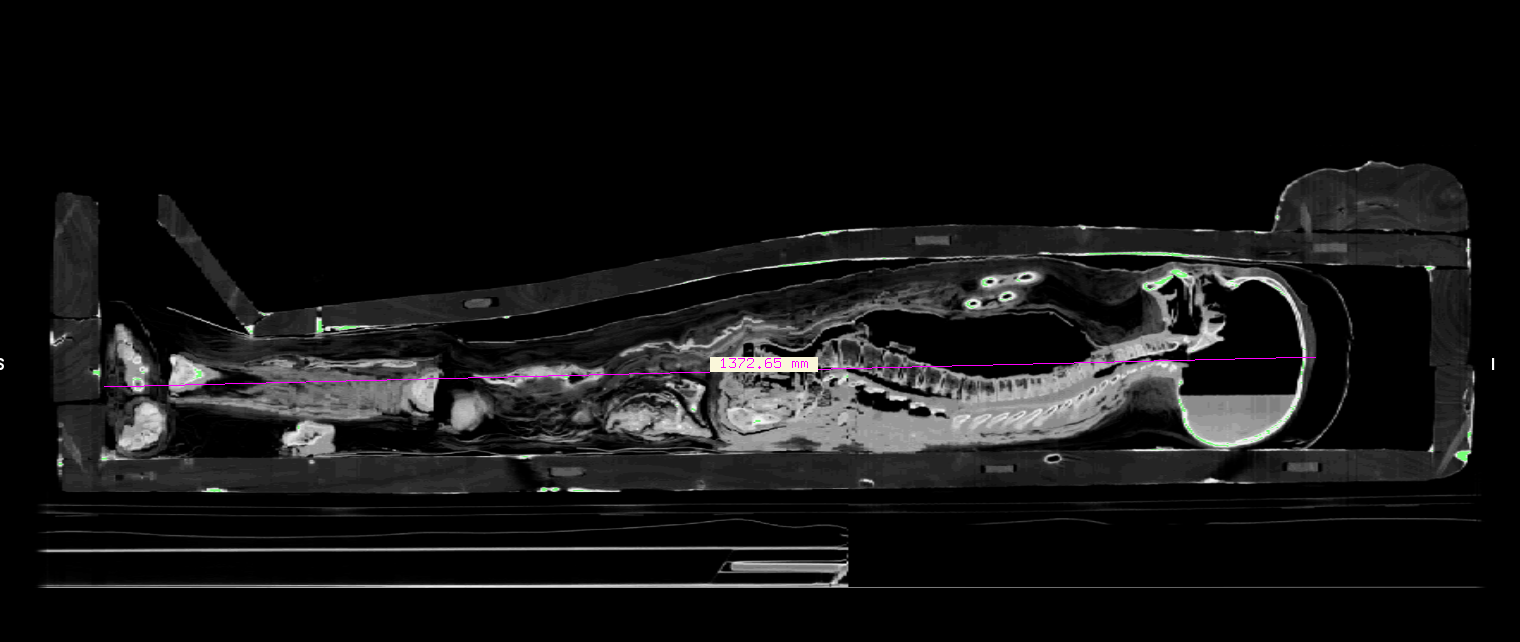

Uma das características interessantes de uma tomografia é que ela podem vir na escala. No caso do menino tive que lançar mão das referências apresentadas no vídeo para colocá-lo na escala correta, e inclusive descobrir a sua altura desidratado, que é de 1.37m. A partir desse dado iniciei a estimativa da idade.